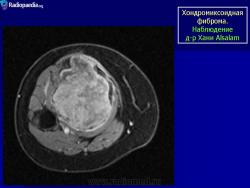

Рентгенологическая картина. Хондромиксоидная фиброма длинных трубчатых костей в типичных случаях представлена метафизарным или метадиафизарным, эксцентричным, четко очерченным, овальным очагом разряжения костной ткани с истон чением и вздутием коркового слоя с одной стороны.

С Радиопедии.